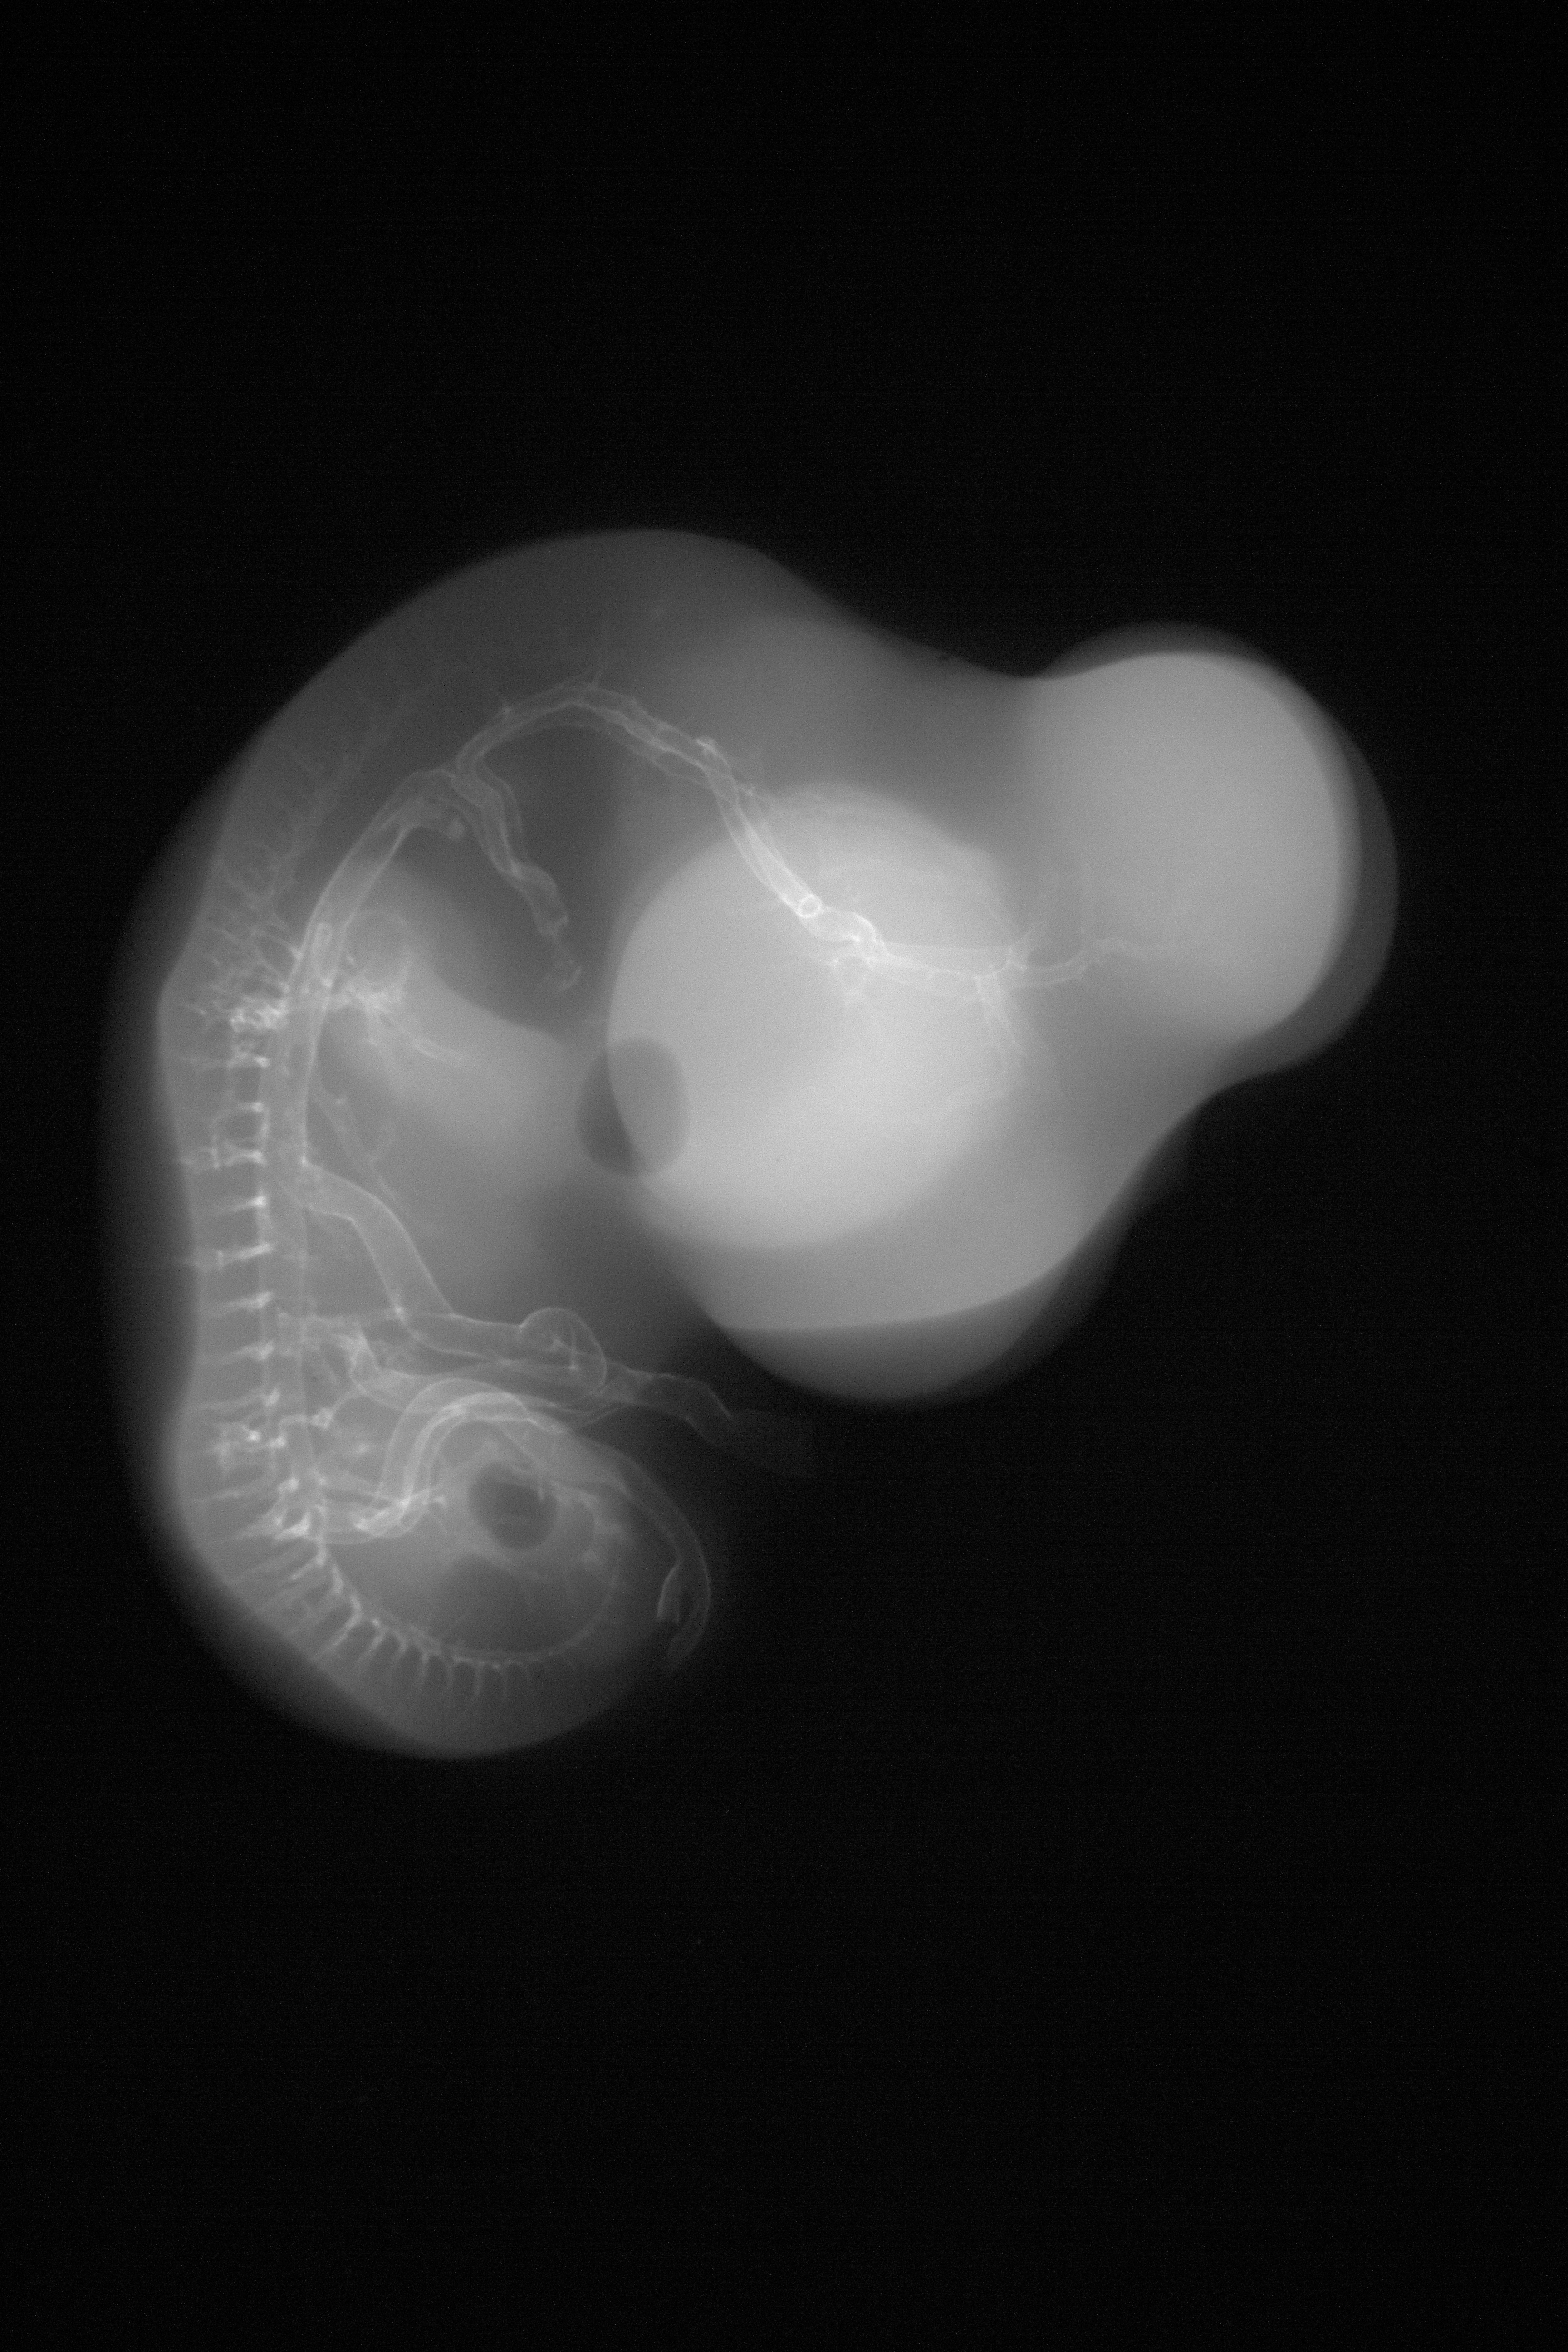

Chick Embryo Microangiography

Hamburger-Hamilton (HH) Stage 28 (approx. 5.5 - 6 days)

X-Ray Micrographs